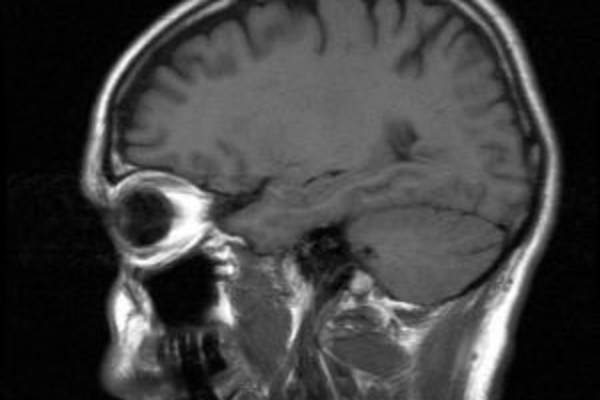

认知能力下降

老年人谁消耗过多的钠含量,但没有得到足够的锻炼可以有提高认知能力下降的风险据最近的一项研究。许多研究发现,钠的摄入会影响心脏健康,但这项研究表明,它可能会影响大脑健康。这项研究表明做出选择健康的生活方式随着人们年龄的重要性,研究人员说。